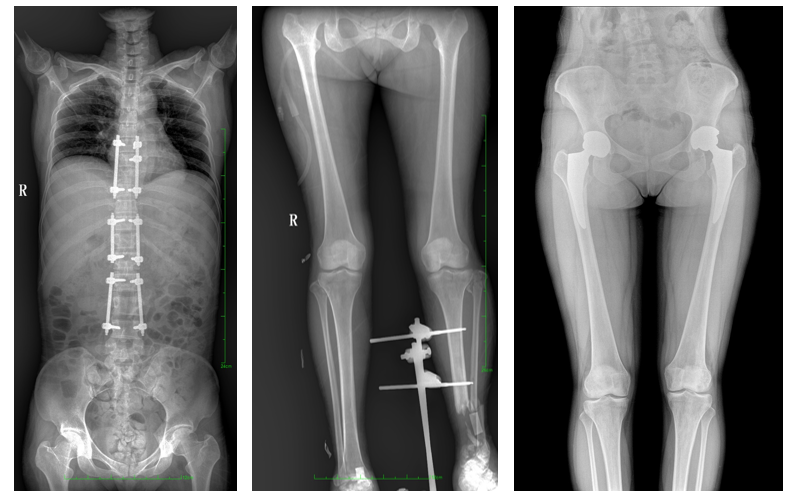

一、成像面积大。17"*34"有效视野,一次成像不拼接。相较于多张摄影再软件拼接的DR设备,PLX8600解决了拼接图像存在密度不均匀,拼接处图像配准和放大效应等问题,给临床带来了大视野影像解决方案,可一次性覆盖全脊柱或双下肢影像。

PLX8600大视野平板动态DR摄影速度快,患者可以更快地完成检查,且单次摄影辐射剂量是常规多张摄影再软件拼接DR的1/2或1/3,低剂量给患者更多关爱。